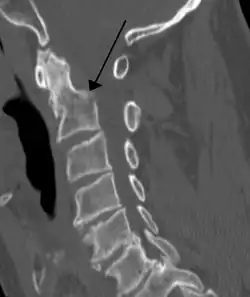

A fracture of the base of the dens as seen on CT

Type 3 odontoid fracture